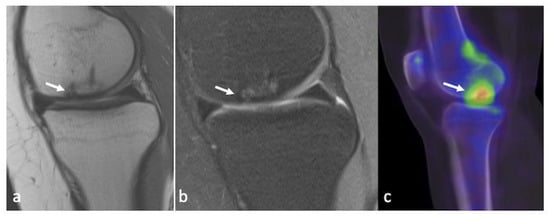

3.5. Integrated PET–MRI